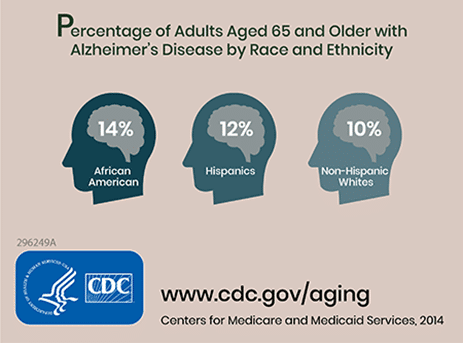

The global incidence of dementia is estimated at 24 million individuals, which is expected to double by 2060. Alzheimer disease is predicted to cost $172 billion in health care costs in the United States annually. After the age of 65, the risk of Alzheimer increases every five years.